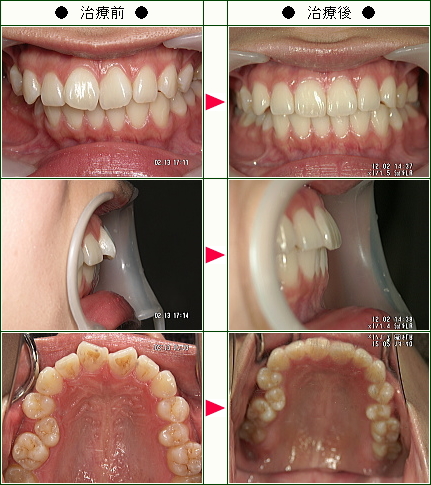

☆歯のデコボコ矯正症例(I様 25歳 女性)